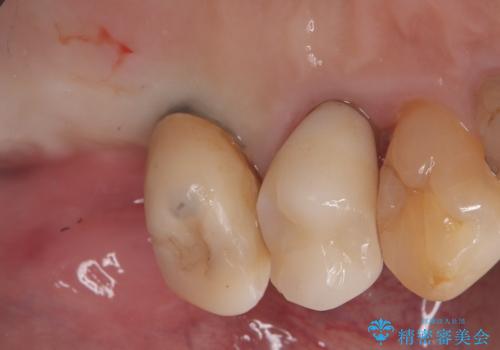

左上6番目の歯が根っこ部分で破折しており、噛むたびに痛みが生じる状態でした。

保存不可能と判断し、抜歯から骨ができるのを3か月待ってインプラント治療を行いました。

歯根破折により抜歯となり、インプラント治療(一回法)にて補綴修復を行いました。

抜歯から3か月程骨ができてくるのを待ってからインプラントを埋入しています。

埋入時には上顎洞粘膜を数ミリ挙上しています。